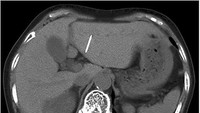

Pemeriksaan CT-scan menunjukkan benda asing mirip jarum menancap miring dari permukaan bawah liver menuju segmen lateral. Tidak tampak adanya nanah maupun tanda infeksi. (Foto: Journal of Surgical Case Reports)